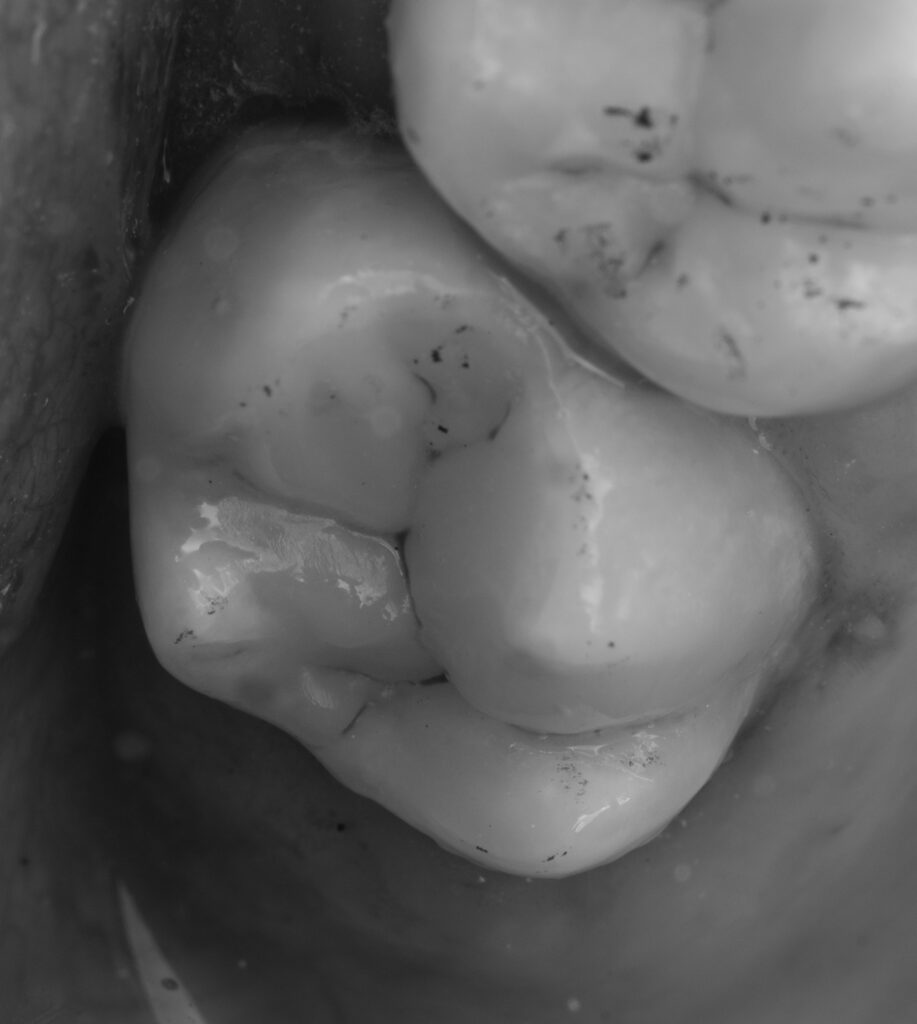

The patient presented with complaints of pain when consuming sweets in tooth 2.7.

A cold test (to determine whether the tooth was vital) and a periapical X-ray were performed before treatment. The patient could open the mouth only up to two fingers wide, which created difficulties with tooth restoration and rubber dam adaptation. EverX Bulk Fill was used due to the large cavity size to help prevent fractures. The enamel surface was restored using NeoSpectra A2 and Asteria A1B.